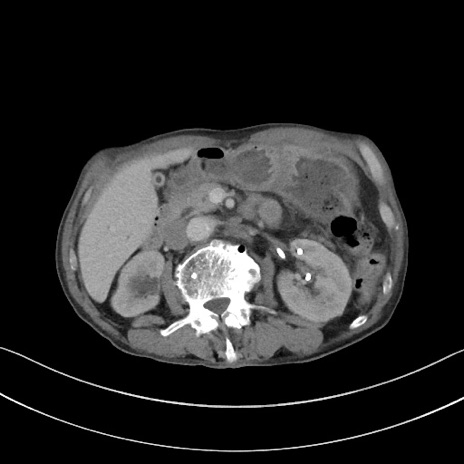

症例3(横断像)

【症例】 70歳代男性

【主訴】右鼠径部腫瘤、疼痛

【現病歴】本日朝より上記主訴あり、受診。

【既往歴】膀胱癌にて膀胱全摘、両側尿管皮膚瘻

【データ】WBC 5600、CRP 0.56